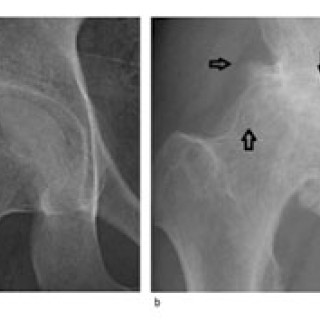

Artrose er sykdom i et synovialt ledd. Det synoviale leddet er et organ bestående av leddbrusk, subkondralt bein og en leddkapsel, som på innsiden er kledd med synovialmembran og på utsiden er forsterket av ligamenter. Sykdommer som primært rammer én av komponentene i et ledd, vil etter hvert medføre sekundære forandringer i de øvrige (fig 1), og det utvikles en leddsvikt som gir pasienten smerter og nedsatt funksjon. Alle ledd kan rammes, men artrose er vanligst i hånd, hofte og kne. Det følgende er en oversikt over epidemiologiske og patologiske forhold, årsaksmekanismer, utredning og...